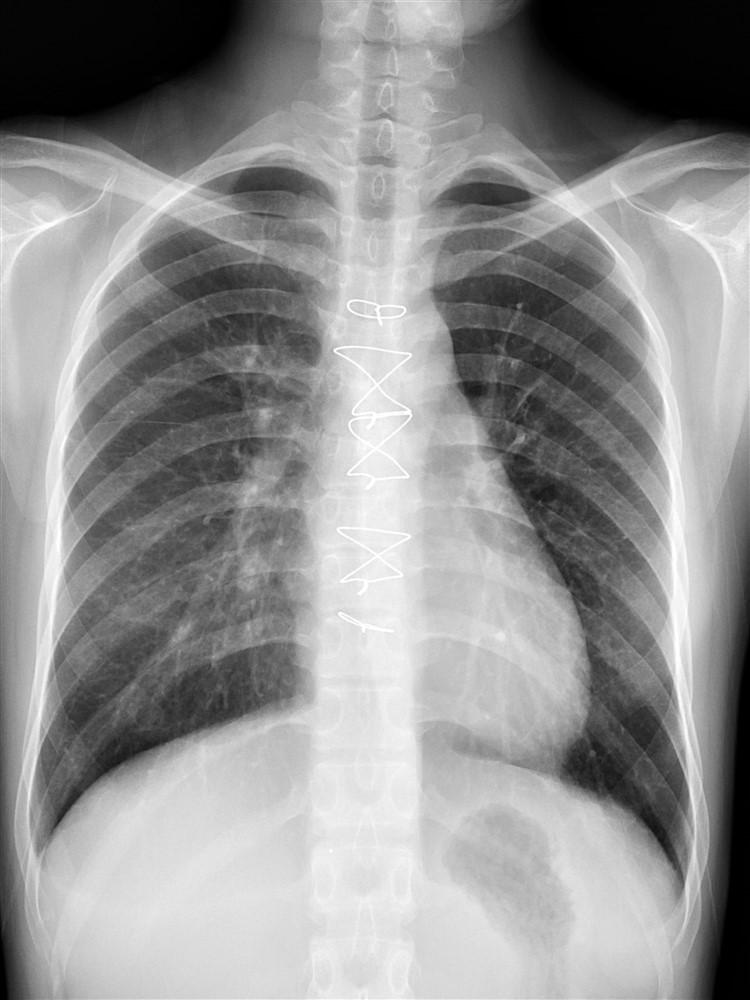

急救隔天,待鄭小姐生命徵象穩定後,心臟外科團隊為她裝上左心室輔助器,並很快地移除葉克膜。由於心室輔助器直接從左心室連結人工血管到主動脈,將左心室的血液抽掉的同時,可以連帶把肺部的血液帶出去,使心臟有效減壓,鄭小姐在換上心室輔助器後心臟功能迅速好轉,隔天即可下床復健和自由活動,十天後就順利拆除心室輔助器。

張睿智主任表示,許多人只知道葉克膜能救命,卻不曉得葉克膜對心臟的危害;而近年來醫療觀念轉變,加上醫療設備的進步,愈來愈多心臟外科醫師更傾向讓急性心衰竭病人盡早由葉克膜換成心室輔助器,加速心臟功能的恢復。花蓮慈院設有二十四小時待命的體外循環小組,以及提供急性和慢性心臟病照護的心臟衰竭團隊,心臟內外科默契合作,救回一條年輕生命。張睿智主任也感恩團隊經年不懈的努力,順利通過醫策會「心衰竭照護品質認證」。